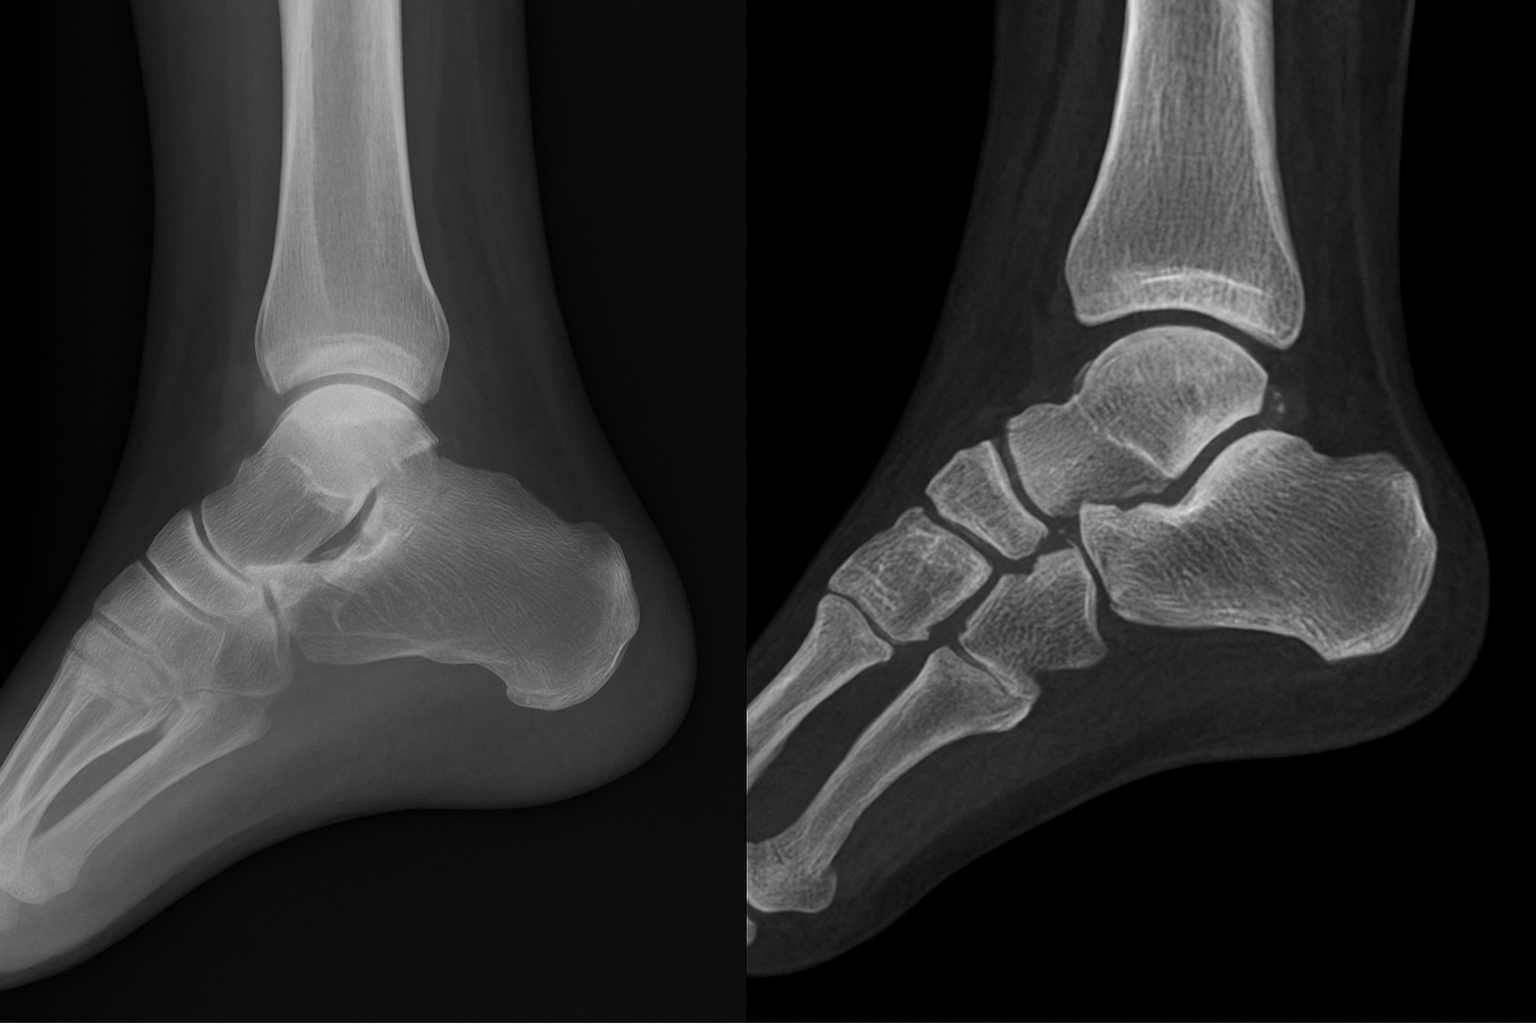

X-ray is the first tool most clinicians reach for when you walk in with foot or ankle pain, and for good reason. It’s fast, widely available, and delivers immediately useful information about bone alignment, joint spacing, and obvious fractures. For the majority of acute injuries and structural concerns, an X-ray gives your podiatrist enough to either confirm a diagnosis or identify what needs a closer look.

What X-rays show and when doctors order them

X-ray uses low-level radiation to produce images of dense structures, primarily bone, with excellent clarity. Your doctor can quickly identify fractures, dislocations, arthritis-related joint narrowing, bone spurs, and deformities like bunions or flatfoot collapse. Foot and ankle imaging that starts with X-ray also helps detect foreign bodies such as glass or metal fragments that may have entered the tissue after a puncture wound.

Your podiatrist will typically order X-rays first when you report a sudden injury, persistent localized bone pain, or a visible deformity. They’re also routine before any surgical planning because they provide a full structural overview of how your bones align and how much space remains between joints. In many cases, a clear X-ray finding is all that’s needed to move forward with a treatment plan without advancing to more complex or expensive studies.

X-ray remains the most practical starting point in foot and ankle imaging because it answers the most common clinical questions quickly and at low cost.

Weight-bearing X-rays and why positioning matters

One detail that separates foot and ankle X-rays from imaging in other body parts is the importance of weight-bearing views. When you stand on your foot and put your full body weight through it, the bones shift into the positions they actually occupy during your daily life. A non-weight-bearing X-ray taken while you’re lying on a table can miss subtle flatfoot deformity, Lisfranc joint instability, or forefoot splay that only become visible under load.

Your technician may take X-rays in multiple positions during a single visit: from the side, from above, and at an angle called the oblique view. Each projection highlights different structures and eliminates the overlap that can hide a small fracture or joint change in a single-angle image. When your clinician reviews all three views together, they build a much more complete picture of your foot’s structure than any single image could provide on its own.